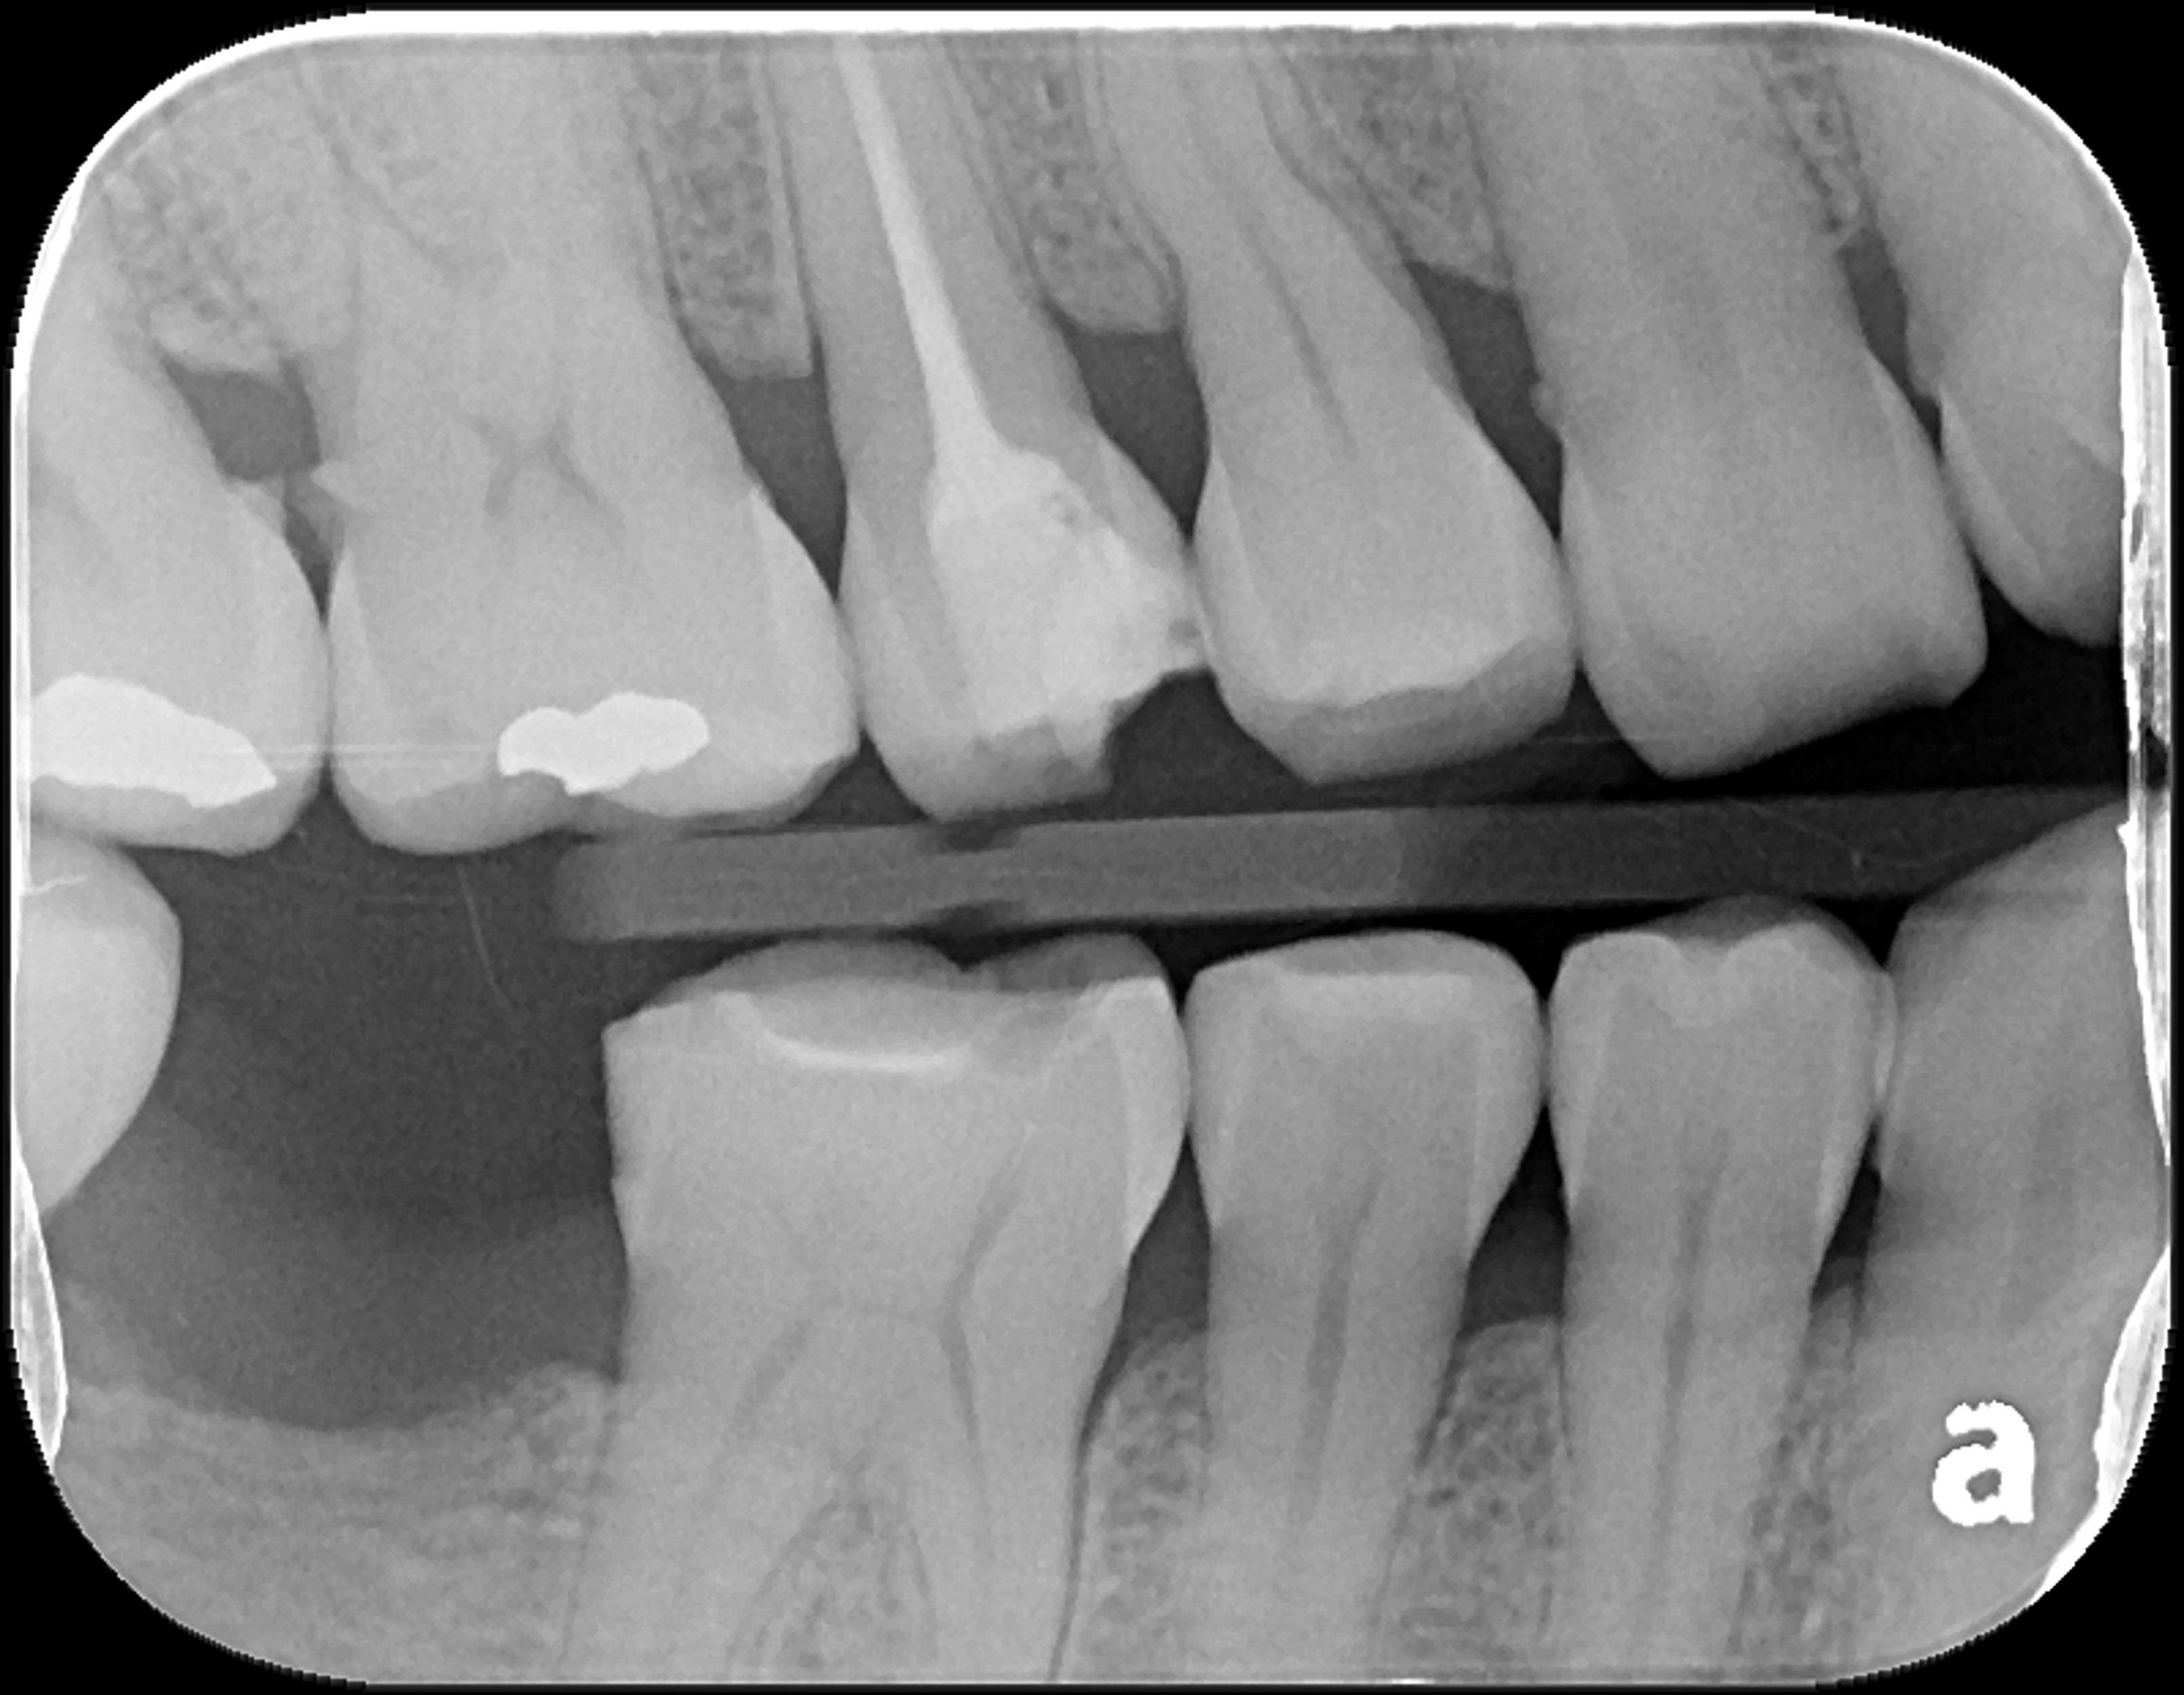

治療前,嚴重二次蛀牙

根管治療後再次牙裂

根尖照,邊緣完整